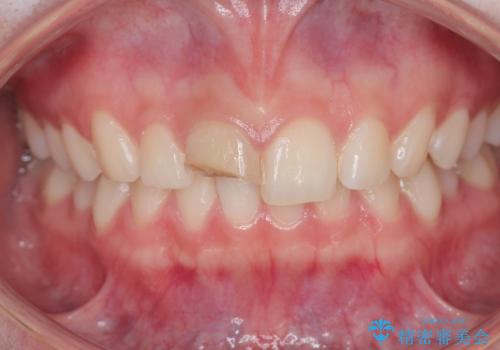

- 前歯が欠けたとの事で来院。

セラミックを希望されたので根管治療からやり直しました。